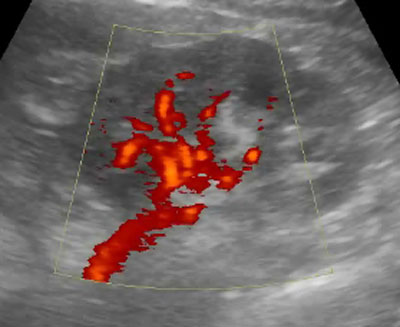

Echographie de la prostate par voie endorectale. Nodule (

) développé aux dépens de la prostate centrale entrainant une déformation du plancher vésical et gênant à la vidange de la vessie. Il existe un résidu postmictionnel intra-vésical.

L’échographie est l’examen de référence pour explorer la prostate et la vessie. En fonction des données cliniques et biologiques, l’autre examen d’imagerie de la prostate est l’IRM.